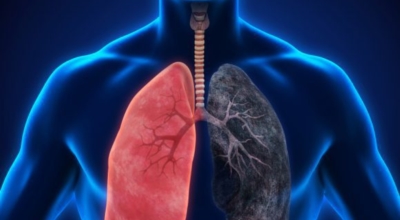

폐에 발생된 악성 종양을 말하며 오랜 기간 흡연해온 남성들에서 발병률이 높고 최근 들어 가지가지 환경적인 요인의 영향과 간접흡연으로 흡연하지 않는 여성에서도 많이 발생하고 있어요. 증상을 느껴 병원을 찾았을 때는 수술하기 늦은 경우가 많아 사망하는 비율이 매우 높은 암입니다. 폐 자체에서 생기거나 다른 장기에서 발생된 암이 폐로 전이되어 나타나기도 하고 특별한 초기 증상이 없는 경우가 많다고 하며 암이 진행된 후에도 일반적인 감기 증상인 기침과 가래 외의 특이 증상이 나타나지않아 증상만으로는 진단이 쉽지 않아요.

폐암의 공통 위험요소로 손꼽히는 까닭으로 흡연이 있어요. 흡연자는 비흡연자에 비교해 십몇 배는 더 폐암 발병확률이 높다고 하며 어느정도 기간 동안 흡연했는지에 따라 폐암 발생확률은 더욱더 더 높아져요. 흡연자라고 해도 금연을 하게 되면 폐암 발병확률이 가파르게 감소한다고 하니 폐암이 걱정되신다면 가장 먼저 금연은 필수입니다.